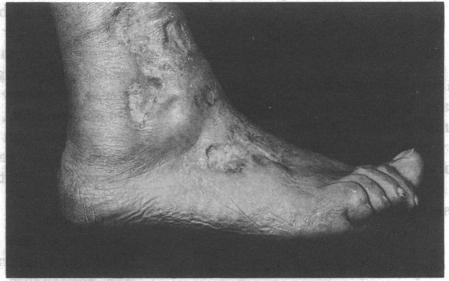

Heparin for uncontrolled disseminated intravascular coagulation in meningococcal septicaemia.

https://cdn.ncbi.nlm.nih.gov/pmc/blobs/ab0b/1292426/fe3700491f92/jrsocmed00143-0076-a.jpg